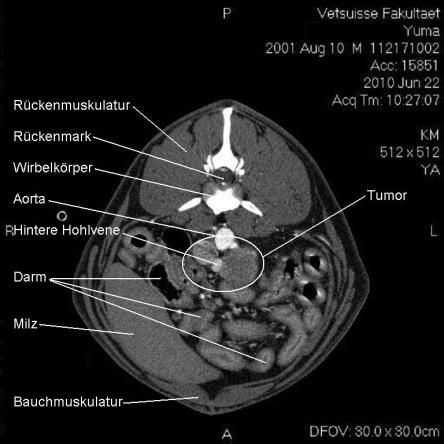

Computertomogramm

Die Computertomographie (CT) liefert mittels eines röntgenähnlichen Verfahrens ein dreidimensionales Bild des untersuchten Körperteils. Da das untersuchte Tier vollständig ruhig liegen muss, wird Yuma zur Untersuchung narkotisiert.

Im CT wird ersichtlich, dass sich der Tumor, welcher von der linken Nebenniere ausgeht, schon sehr weit in das Gefässystem von Yuma vorgearbeitet hat. Krebsausläufer finden sich wie erwartet in der Hohlvene, aber auch in der Nierenvene sowie in einer weiteren grossen Vene. Der Geschwulst ist somit inoperabel.